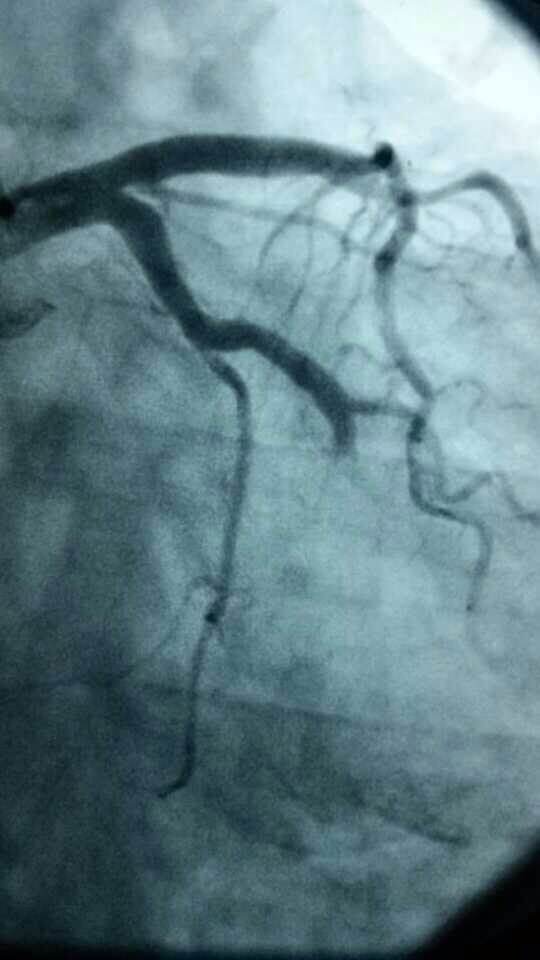

心脏有问题不可麻痹大意。急性胸痛的病人往往病情凶险,抢得时间就能挽救生命。今天,伦理片

心内科医务人员在崔勇主任的带领下,蔡亚滨、林福根、雷建林、陈明辉、何晓、李仲伟等抢救团队连续奋战 8个小时成功抢救3名心梗患者。虽然工作艰辛,但接诊的三位病人都能转危为安,对医生来讲是最大的安慰。